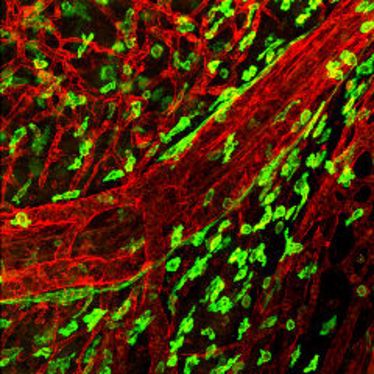

Verleihung des Pro Scientia Preises und Festvorträge der Preisträger Lydia Sorokin und Thomas Pap

Verleihung des Pro Scientia Preises und Festvorträge der Preisträger Lydia Sorokin und Thomas Pap

Vortrag des SFB 492: Extrazelluläre Matrix

Vortrag des SFB 492: Extrazelluläre Matrix